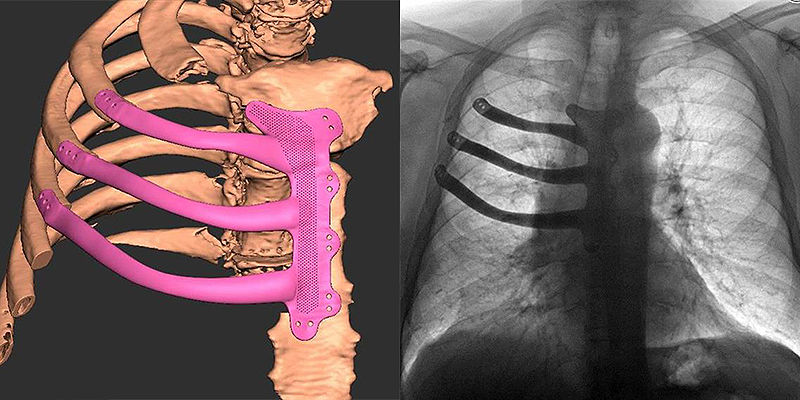

Dienvidu Moristonas slimnīcā Velsā tika izņemts Maggsa drausmīgais tenisa bumbas lieluma audzējs, un, pirmoreiz mazajā valstī, kas ietilpst Apvienotajā Karalistē, tika izmantota 3D printēšanas tehnoloģija, lai atjaunotu vecā vīra krūškurvi.

3D printētās protēzes dizains tika balstīts uz pacienta krūšu kaulu datorskenēšanu, un to izstrādāja 3D tehniķe Hīzera Gudrama (Heather Goodrum), kura pagājušajā gadā kļuva par Lielbritānijas pirmo medicīnisko 3D drukas tehniķi NHS (valsts veselības aprūpes dienesta) slimnīcā, un galvas un sejas laboratorijas pakalpojumu menedžeris Pīters Levlins Evanss (Peter Llewelyn Evans).

Krūškurvja implants tika 3D printēts no titāna Lielbritānijas 3D printēšanas ražošanas uzņēmumā Renishaw, kas oktobrī atklāja savu četru lāzeru 3D printeri RenAM 500Q.

Neparasti ir tas, ka titāna krūškurvja implants bija jāpiešuj krūšu kaulam, nevis jāpieskrūvē, jo šis kauls ir šaurs un

mīksts, un to viegli var saplēst zem skrūves spiediena. Pēc tam implants tika pārklāts ar latissimus dorsi muskuļu daļu, kas ņemta no Maggs muguras vidusdaļas.

(Attēls: ABMU Health Board)